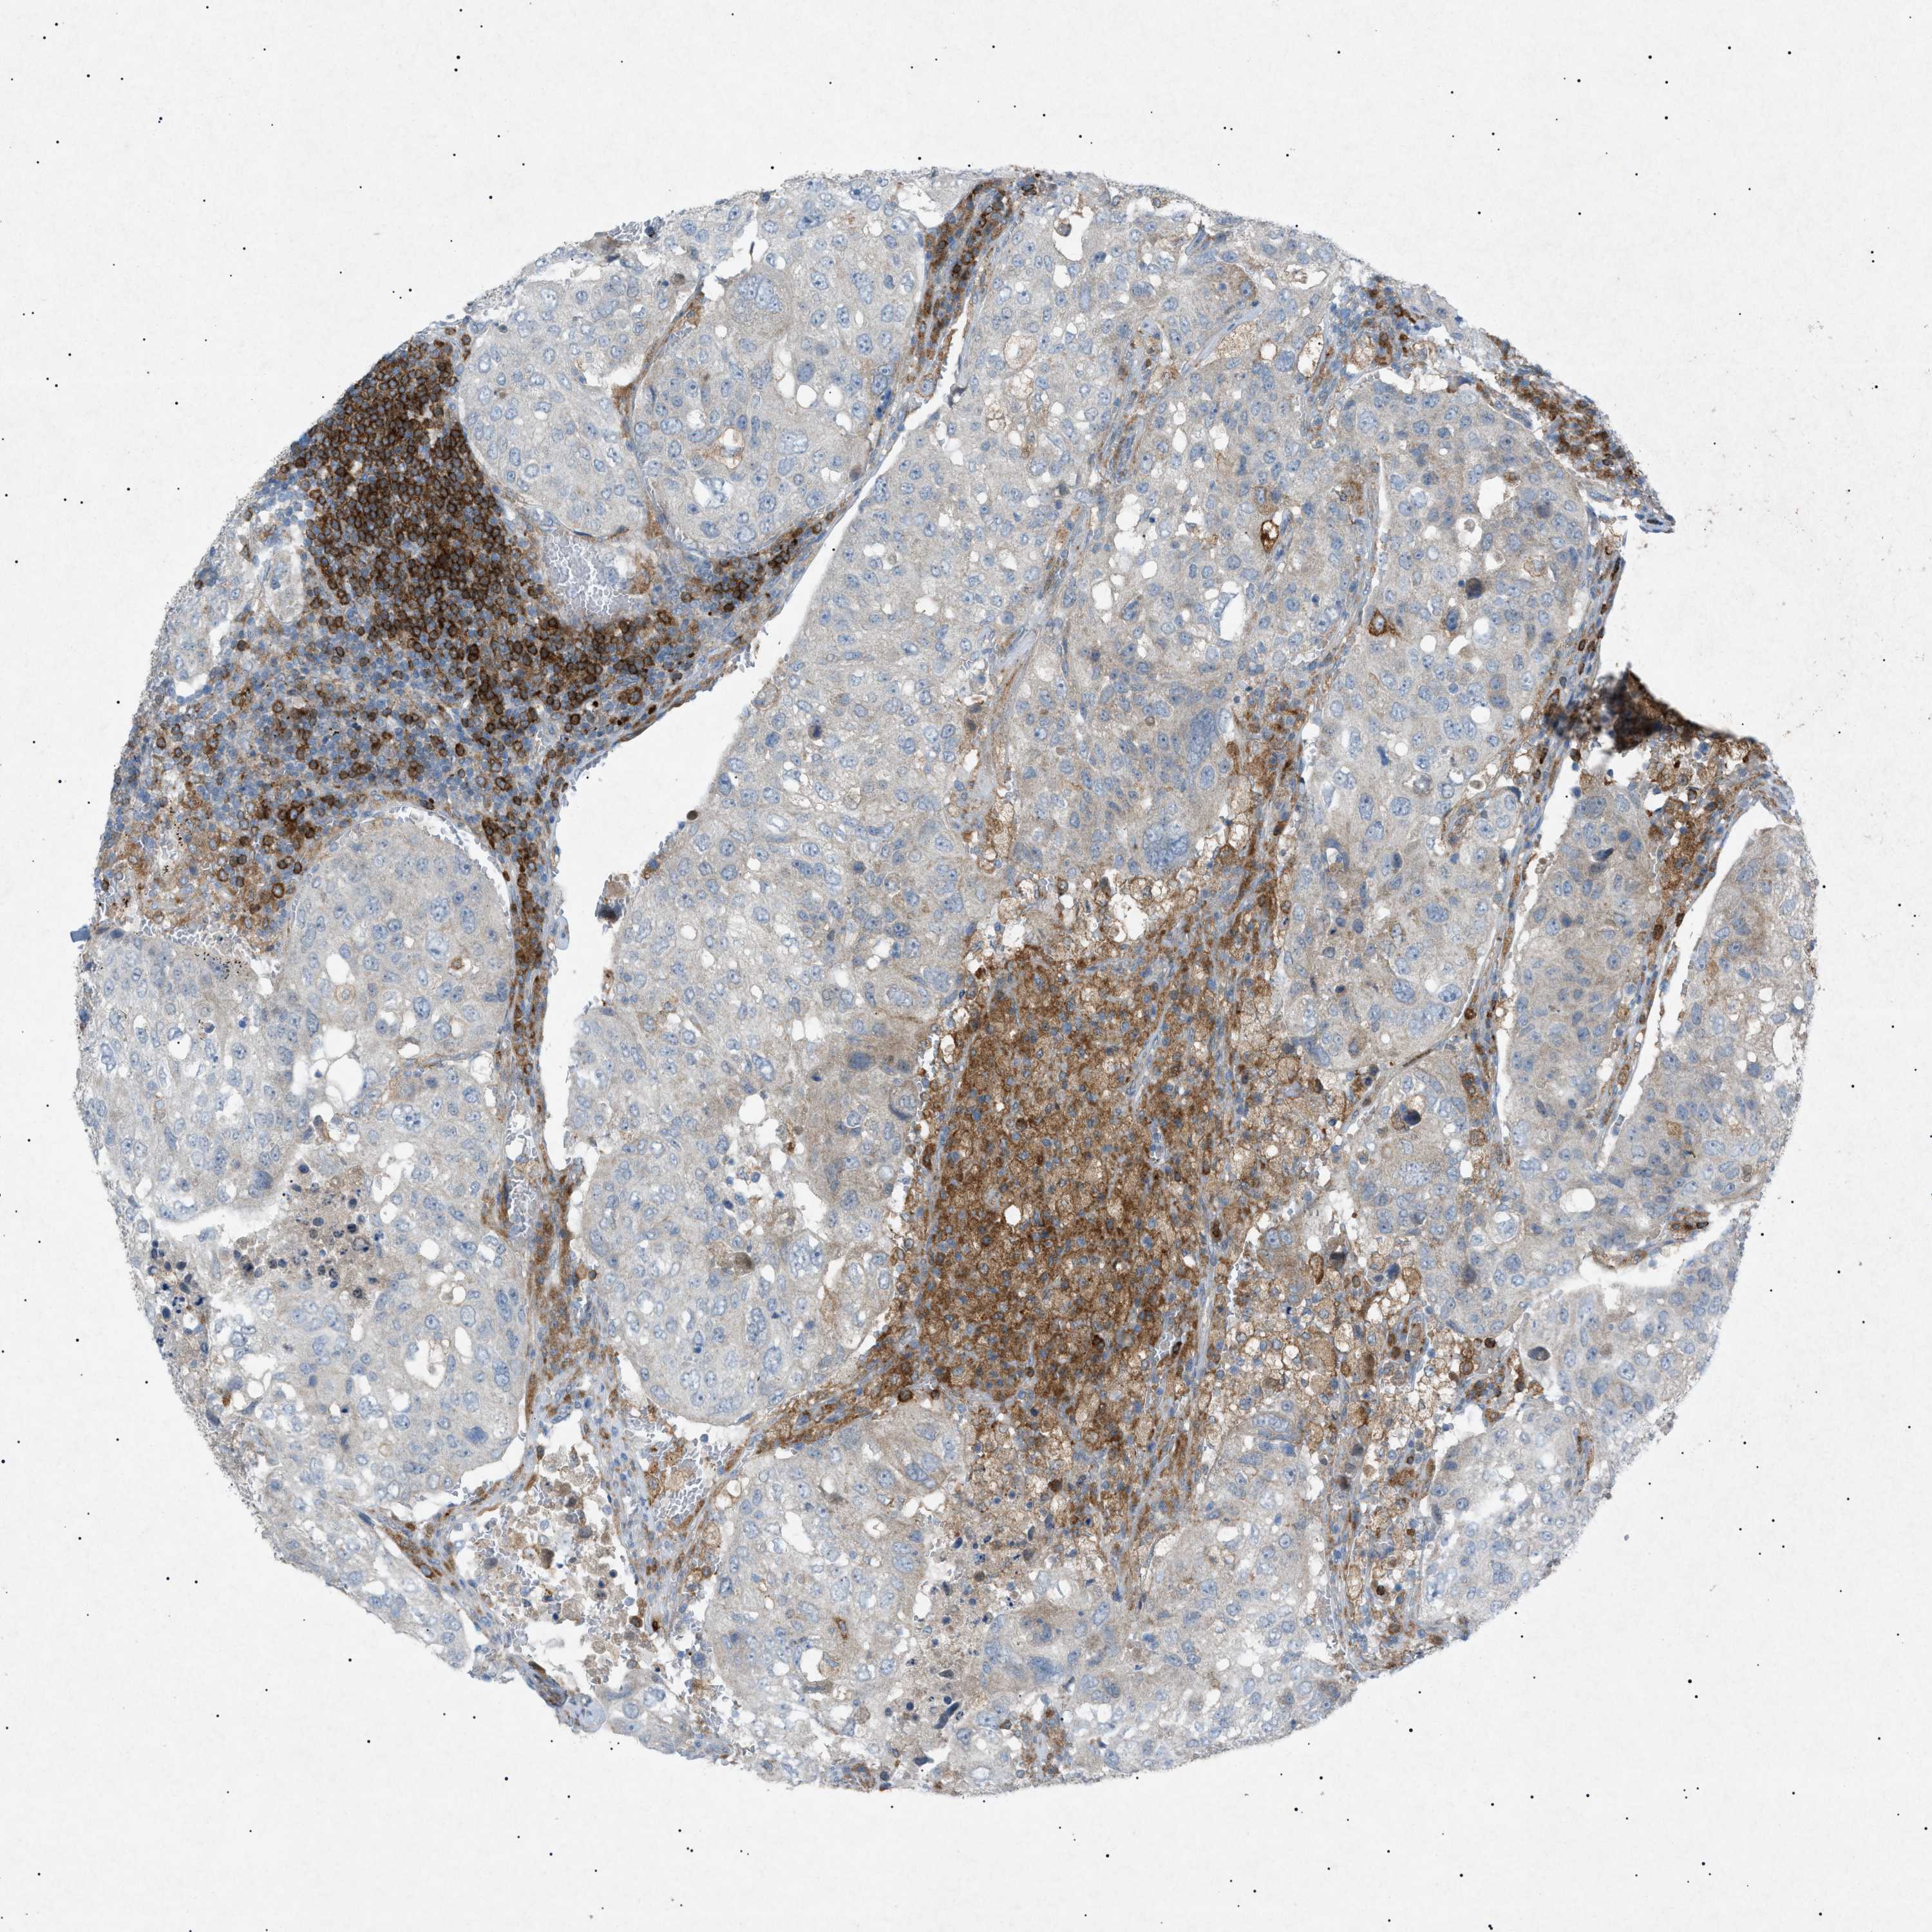

UROTHELIAL CANCER - Protein expressioni

A mouse-over function shows sample information and annotation data. Click on an image to view it in a full screen mode. Samples can be filtered based on level of antibody staining by selecting one or several of the following categories: high, medium, low and not detected. The assay and annotation is described here.

Note that samples used for immunohistochemistry by the Human Protein Atlas do not correspond to samples in the TCGA dataset.

Antibody stainingi

Antibody staining in the annotated cell types in the current human tissue is reported as not detected, low, medium, or high, based on conventional immunohistochemistry profiling in selected tissues. This score is based on the combination of the staining intensity and fraction of stained cells.

Each image is clickable and will lead to virtual microscopy that enables deeper exploration of all samples and also displays staining intensity scores, fraction scores and subcellular localization as well as patient and tissue information for each sample.

Antibody HPA001198

Antibody HPA002028

Antibody CAB016689

Antibody CAB080300

Staining

High

Medium

Low

Not detected

Intensity

Strong

Moderate

Weak

Negative

Quantity

>75%

75%-25%

<25%

None

Location

Nuclear

Cytoplasmic/membranous

Cytoplasmic/membranous,nuclear

Urothelial carcinoma, High grade

Urothelial carcinoma, Low grade

Adenocarcinoma, NOS